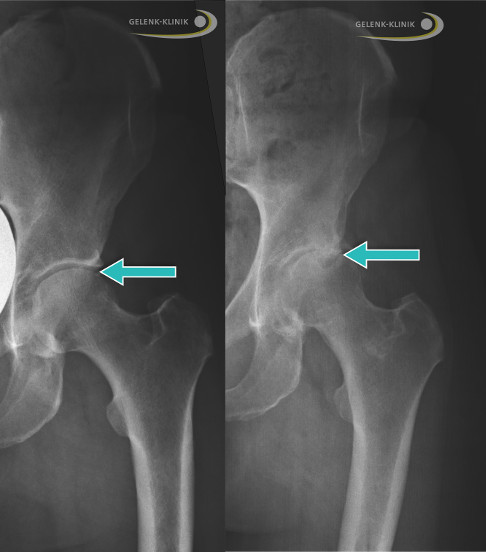

Die Röntgenuntersuchung ist die Standarddiagnostik der Hüftarthrose. Das im Stehen unter Belastung aufgenommene Röntgenbild lässt Rückschlüsse auf die verschiedenen Stadien der Hüftarthrose zu. Man spricht hier von einer funktionellen Diagnostik, die die Funktion des Hüftgelenks überprüft. Unter Gewichtsbelastung hält nur die funktionierende Knorpelschicht im Hüftgelenk die beiden beteiligten Gelenkpartner mit einem sichtbaren Gelenkspalt auf Abstand. Je nach Stadium der Arthrose verschmälert sich der Gelenkspalt also bei zunehmendem Knorpelverschleiß immer weiter. Im Stadium 4 der Hüftarthrose ist der Gelenkspalt schließlich ganz verschwunden: Oberschenkelkopf und Hüftpfanne liegen bei schwerer Hüftarthrose direkt aufeinander.

- Ist der Gelenkspalt verschmälert?

- Sind Hüftkopf und Gelenkpfanne normal geformt?

- Ist der Knochen unter dem Knorpel verstärkt (sklerosiert)?

- Ist der Knochen über flüssigkeitsgefüllten Hohlräumen (Geröllzysten) eingebrochen?

- Gibt es freie Gelenkkörper?

- Haben sich Knochenstücke aus Nekrosebezirken (abgestorbenes Knochengewebe) nahe der Gelenkfläche abgelöst (Osteochondrosis dissecans)?

- Verbreitert sich der Knochen im Gelenk durch dornförmige Osteophyten?

Untersuchung der Hüftarthrose mittels MRT